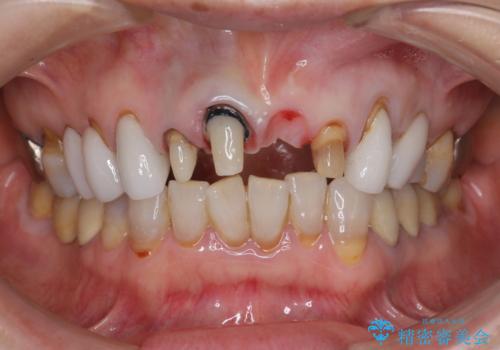

[ セラミック治療 ] 歯ぐきの際の黒ずみを改善したい

- 歯ぐきとセラミックの間の黒ずみが目立つので、きれいに治してほしい。と希望され来院されました。

歯ぐきの位置が変化しクラウン下の歯が見えるようになってしまったことで、審美障害が生じている状態です。

クラウンマージンの再設定を行うことで、黒ずんだ部分を再度覆い、審美障害を改善します。